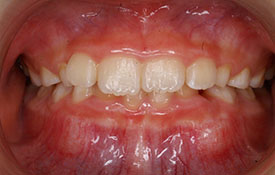

| プロフィール | 42歳 女性 |

| 所見 | 他院で行われた矯正歯科治療後の後戻りに悩まれて来院されました。 アイライナーの装着は、1日平均20時間ほどでした。 |